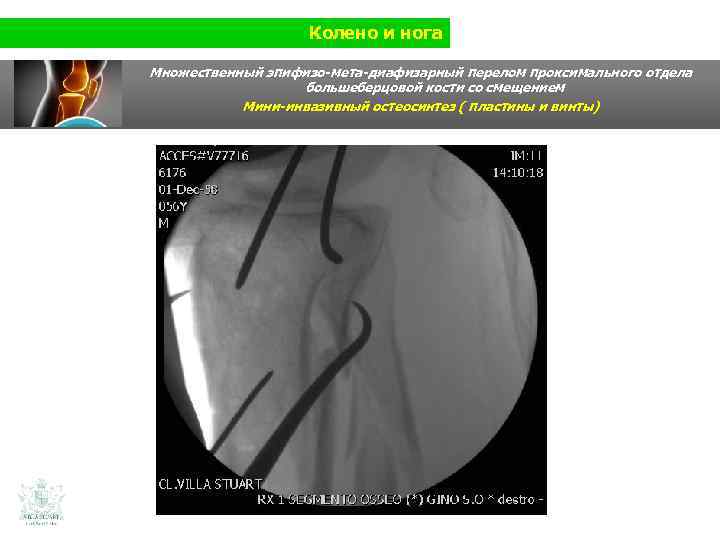

Колено и нога Множественный эпифизо-мета-диафизарный перелом проксимального отдела большеберцовой кости со смещением (Shatzer 6) Мини-инвазивный остеосинтез ( пластины и винты)

Колено и нога Множественный эпифизо-мета-диафизарный перелом проксимального отдела большеберцовой кости со смещением Мини-инвазивный остеосинтез ( пластины и винты)

Колено и нога Множественный эпифизо-мета-диафизарный перелом проксимального отдела большеберцовой кости со смещением Мини-инвазивный остеосинтез (пластины и винты)